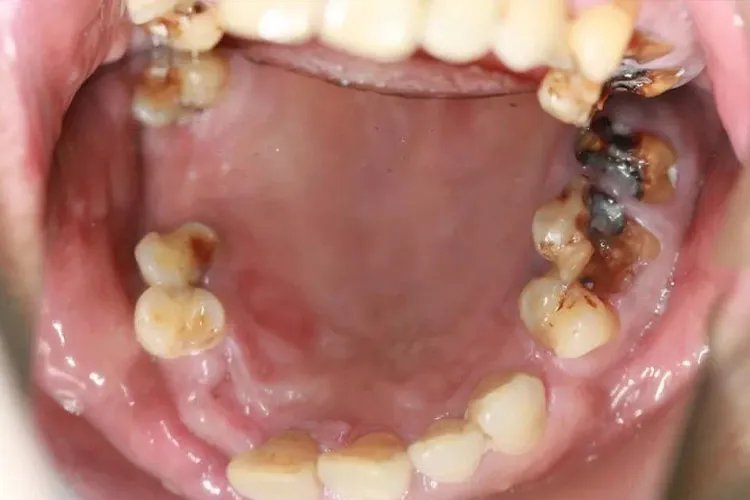

深龋深龋一般表现为大而深的龋洞,或入口小而深层有较为广泛的破坏,对外界刺激反应较中龋为重,患者会有明显的口腔异味。